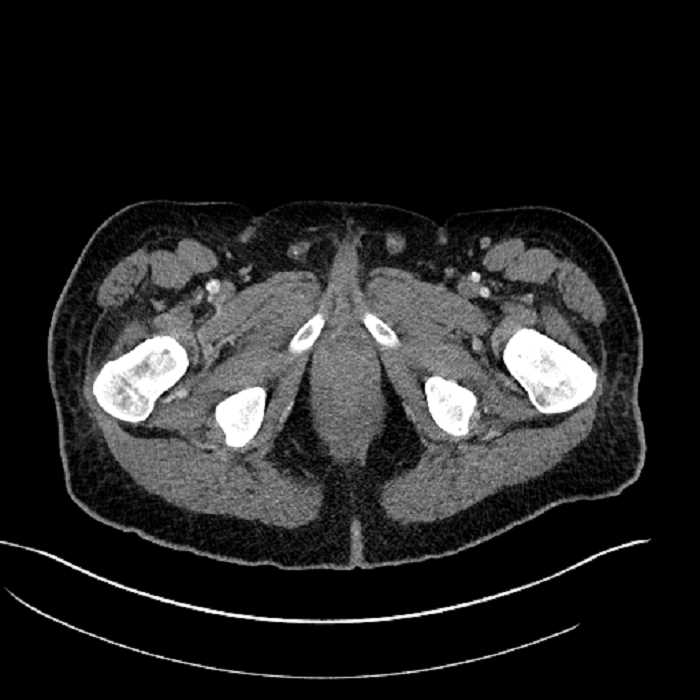

Age: 63

Sex: Male

Indication: Abdominal pain

• High grade stenosis of the left common iliac artery, with the left internal and external iliac arteries remaining patent

• Ankylosis of both sacroiliac joints

Acute sigmoid diverticulitis complicated by a small contained perforation and a large abscess in the right hepatic lobe. Additional small subcapsular abscesses along the anterior margin of the left hepatic lobe.

High grade stenosis of the left common iliac artery. The left external and internal iliac arteries are patent.

Hepatic abscess showing the double target sign with low density internally surrounded by a thin inner enhancing rim (red arrow) and ill-defined outer low density rim (yellow arrow). Blue arrow indicates an internal septation. Red arrows: additional smaller subcapsular abscesses. Red arrow: focal contained perforation associated with diverticulitis.